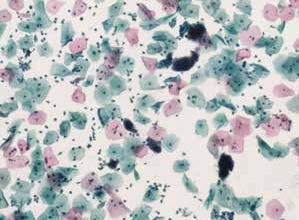

图2-2 细菌性阴道病(高倍、液基、巴氏染色)

覆盖在表层和中间层鳞状上皮细胞表面的细菌(主要为球菌,嗜碱性,取代乳酸杆菌),看似一个绒球,为线索细胞。液基制片中背景相对清晰。

图2-3 细菌性阴道病(中倍、液基、巴氏染色)

多量线索细胞和炎细胞,球菌和线索细胞是细菌性阴道病的主要细胞学表现。

细菌性阴道病是最常见的妇科感染,主要由于乳酸杆菌缺乏导致阴道pH值增加,使其他球菌或杆菌得以生长。朦胧的背景,小的球状杆菌,鳞状细胞表面覆盖着许多细菌,主要为球菌,嗜碱性,使细胞表面和细胞轮廓模糊不清,像有薄膜覆盖,这种特殊形态的细胞称为线索细胞(clue cells)。显微镜下查见线索细胞,报告菌群失调,提示细菌性阴道病。